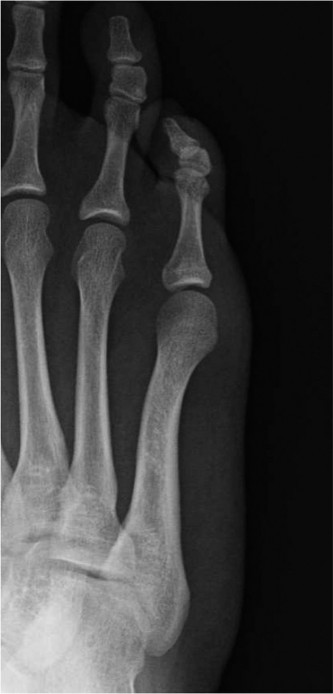

An otherwise healthy 19-year-old female presents with a 6-week history of progressive pain over the lateral a…